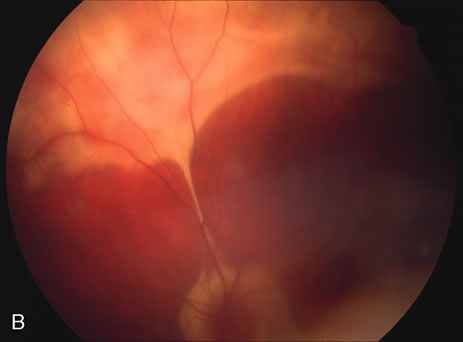

Some patients present with subretinal bands that extend between chorioretinal scars. In addition there may be initial active yellow choroidal lesions that subsequently become atrophic. Vitreous cells are usually present although they may be few and difficult to detect. Visual acuity loss in these cases may be due to active choroidal neovascularization, subretinal bands under the fovea, or from cystoid macular edema. The vast majority of affected patients are women with a mean age of 27 years and both eyes are usually involved. The affected individuals tend to be myopic.49 The age range is from 6 years to 76 years and there is no racial predilection.40 Whether it is a separate disease or a more severe form of multifocal choroiditis is controversial (Figs. 10 and 11). Aggressive therapy is warranted because it has a poorer prognosis than most cases of multifocal choroiditis. This syndrome has been called either diffuse subretinal fibrosis or progressive subretinal fibrosis syndrome.

Fig. 11. A. Subretinal fibrosis in a case of multifocal choroiditis. B. Fellow eye showing classic coalescent hyperpigmented chorioretinal scars of multifocal choroiditis. These scars also can be seen in presumed histoplasmosis syndrome, but the subretinal fibrosis is extremely rare in presumed ocular histoplasmosis syndrome (POHS).